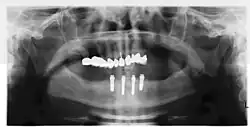

Four mandibular implants

Four lower implants to retain a complete denture with novaloc abutments

Panorex radiograph showing implants

Xray of four Straumann implants and abutments

When a removable denture is worn, retainers to hold the denture in place can be either custom made or "off-the-shelf" (stock) abutments. When custom retainers are used, four or more implant fixtures are placed and an impression of the implants is taken and a dental lab creates a custom metal bar with attachments to hold the denture in place. Significant retention can be created with multiple attachments and the use of semi-precision attachments (such as a small diameter pin that pushes through the denture and into the bar) which allows for little or no movement in the denture, but it remains removable.[30]: 33–34  However, the same four implants angled in such a way to distribute occlusal forces may be able to safely hold a fixed denture in place with comparable costs and number of procedures giving the denture wearer a fixed solution.[79]

Alternatively, stock abutments are used to retain dentures using a male-adapter attached to the implant and a female adapter in the denture. Two common types of adapters are the ball-and-socket style retainer and the button-style adapter. These types of stock abutments allow movement of the denture, but enough retention to improve the quality of life for denture wearers, compared to conventional dentures.[80] Regardless of the type of adapter, the female portion of the adapter that is housed in the denture will require periodic replacement, however the number and adapter type does not seem to affect patient satisfaction with the prosthetic for various removable alternatives.[81]